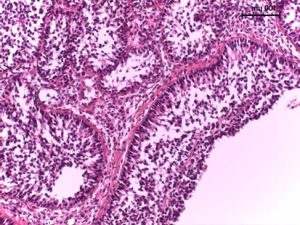

Cel: diagnostyka ziarniszczaka (GCT) u klaczy oraz wnętrostwa/pozostałości tkanki jąder u samców, kontrola po kastracji (

)

komórki granulozy pęcherzyków jajnikowych (małych pęcherzyków, w dużych pęcherzykach przedowulacyjnych spadek syntezy AMH)

komórki Sertoliego kanalików nasiennych w jądrze

brak rui lub nieregularne cykle (ciąża i cykle płciowe nie wykluczają występowania GCT)

zmiany zachowania – od nimfomanii po zachowania ogierze, ale często bez zmian

zwykle jeden jajnik znacznie powiększony, drugi nieaktywny (mieć na uwadze, że guzy mogą być obustronne)

wyższe prawdopodobieństwo u klaczy w wieku >10 lat, jednak możliwy w każdym wieku

brak obecności jądra/jąder w mosznie przy istniejących zachowaniach ogierzych

predyspozycje rasowe do wnętrostwa zwłaszcza u American Quarter Horse, perszerony

Agresywne zachowania bywają często interpretowane jako objaw obecności ziarniszczaka lub aktywnej tkanki jądra, jednak badania wskazują, że korelacja ta jest słaba. W takich przypadkach diagnostyka oparta na testach laboratoryjnych jest obiektywnym narzędziem, pomocnym zwłaszcza w przypadku niejednoznacznej prezentacji w badaniach obrazowych/palpacyjnych.